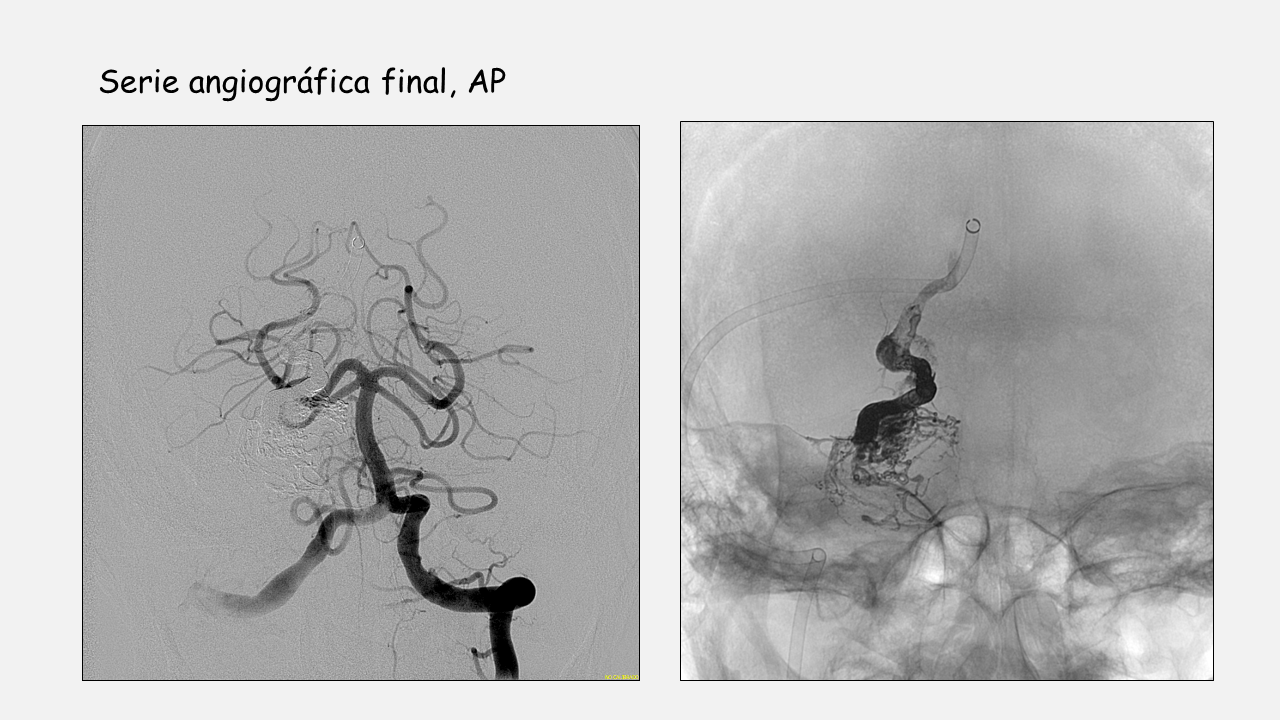

Estrategia y resumen de la intervención.

- MAV rota con aneurisma de flujo y nidal (elevado riesgo de resangrado) dependientes de arterias perforantes de difícil cateterismo.

- Al presentar una vena de drenaje única se procede a la embolización vía venosa utilizando microcatéter con punta desprendible y técnica de olla a presión.

- El objetivo de la embolización es que el agente embolizante ocluya el pie de vena con el menor reflujo posible y penetre en el nidus y en la parte distal de los pedículos arteriales para evitar sangrados postembolización.

- El pie de vena no es ciego por lo que se emboliza su trayecto distal para evitar la progresión del agente embolizante hacia esa vena.

- Posteriormente se colocan coils en la parte proximal de la vena y se inicia la inyección de agente embolizante de mayor densidad (18) hasta que se rellena todo el pie de vena. En este momento se inyecta pegamento al 50% para sellar la zona venosa donde están los coils y la parte proximal libre de coils (Técnica de la olla a presión).

- Se continúa la inyección de agente embolizante de menor densidad (12) que penetra en el nidus (se observa relleno y cierre del aneurisma nidal) y progresa hacia los pedículos arteriales (se observa desaparición por efecto de flujo del aneurisma de flujo en a. perforante).

- No se identifica reflujo hacia el pedículo de la AICA y en las series de control se identifica resto de MAV en esa zona por lo que, para evitar sangrados postembolización, se procede a la embolización vía arterial del pedículo dependiente de la AICA.